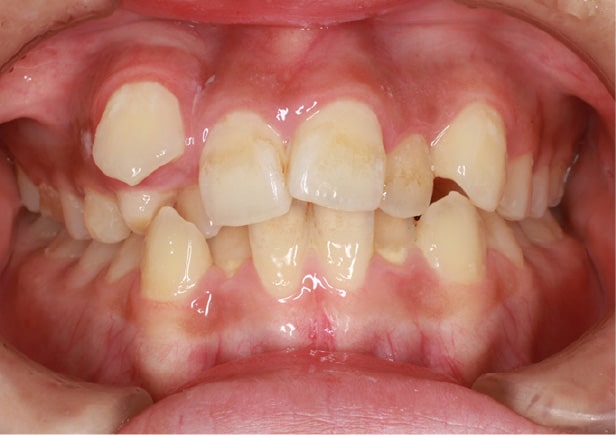

• 症例2

矯正bofore

矯正種類 ワイヤー矯正

症例 上下額叢生

治療期間 2021年12月〜2024年10月

性別/年代 男 13歳

治療費 748,000円

コメント

適切な時期に治療が開始できたので、歯並びだけでなく顎や顔貌も理想的に成長しました。歯磨きもしっかりできるようになりました。